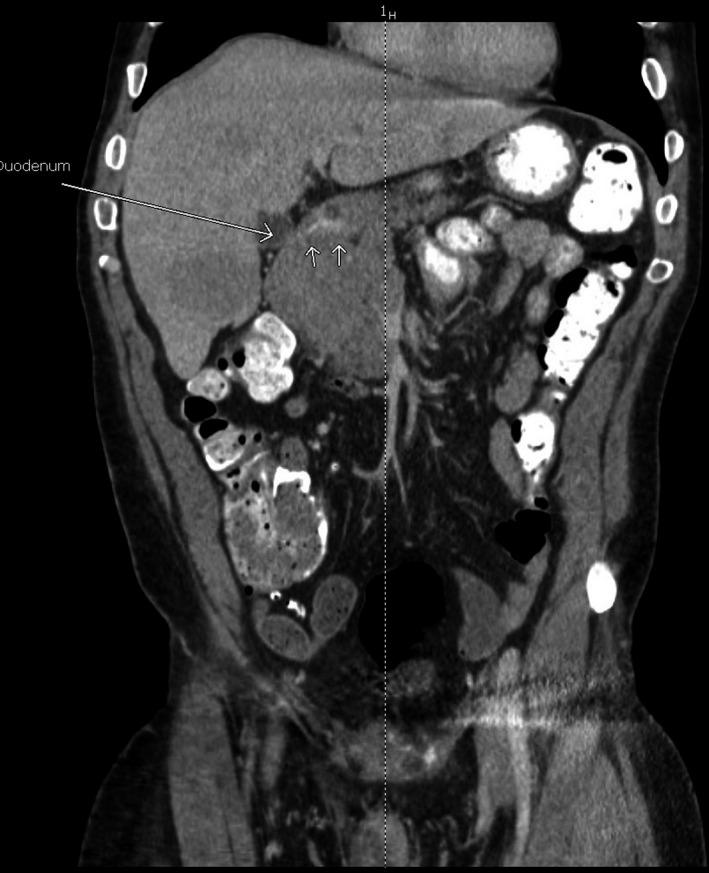

脂肪酶分泌过多综合征:晚期胰腺腺泡细胞癌的一种罕见皮肤表现。

Lipase hypersecretion syndrome: A rare cutaneous manifestation of advanced pancreatic acinar cell carcinoma.

Clin Case Rep. 2020 Mar 12;8(5):905-910. doi: 10.1002/ccr3.2785. eCollection 2020 May.